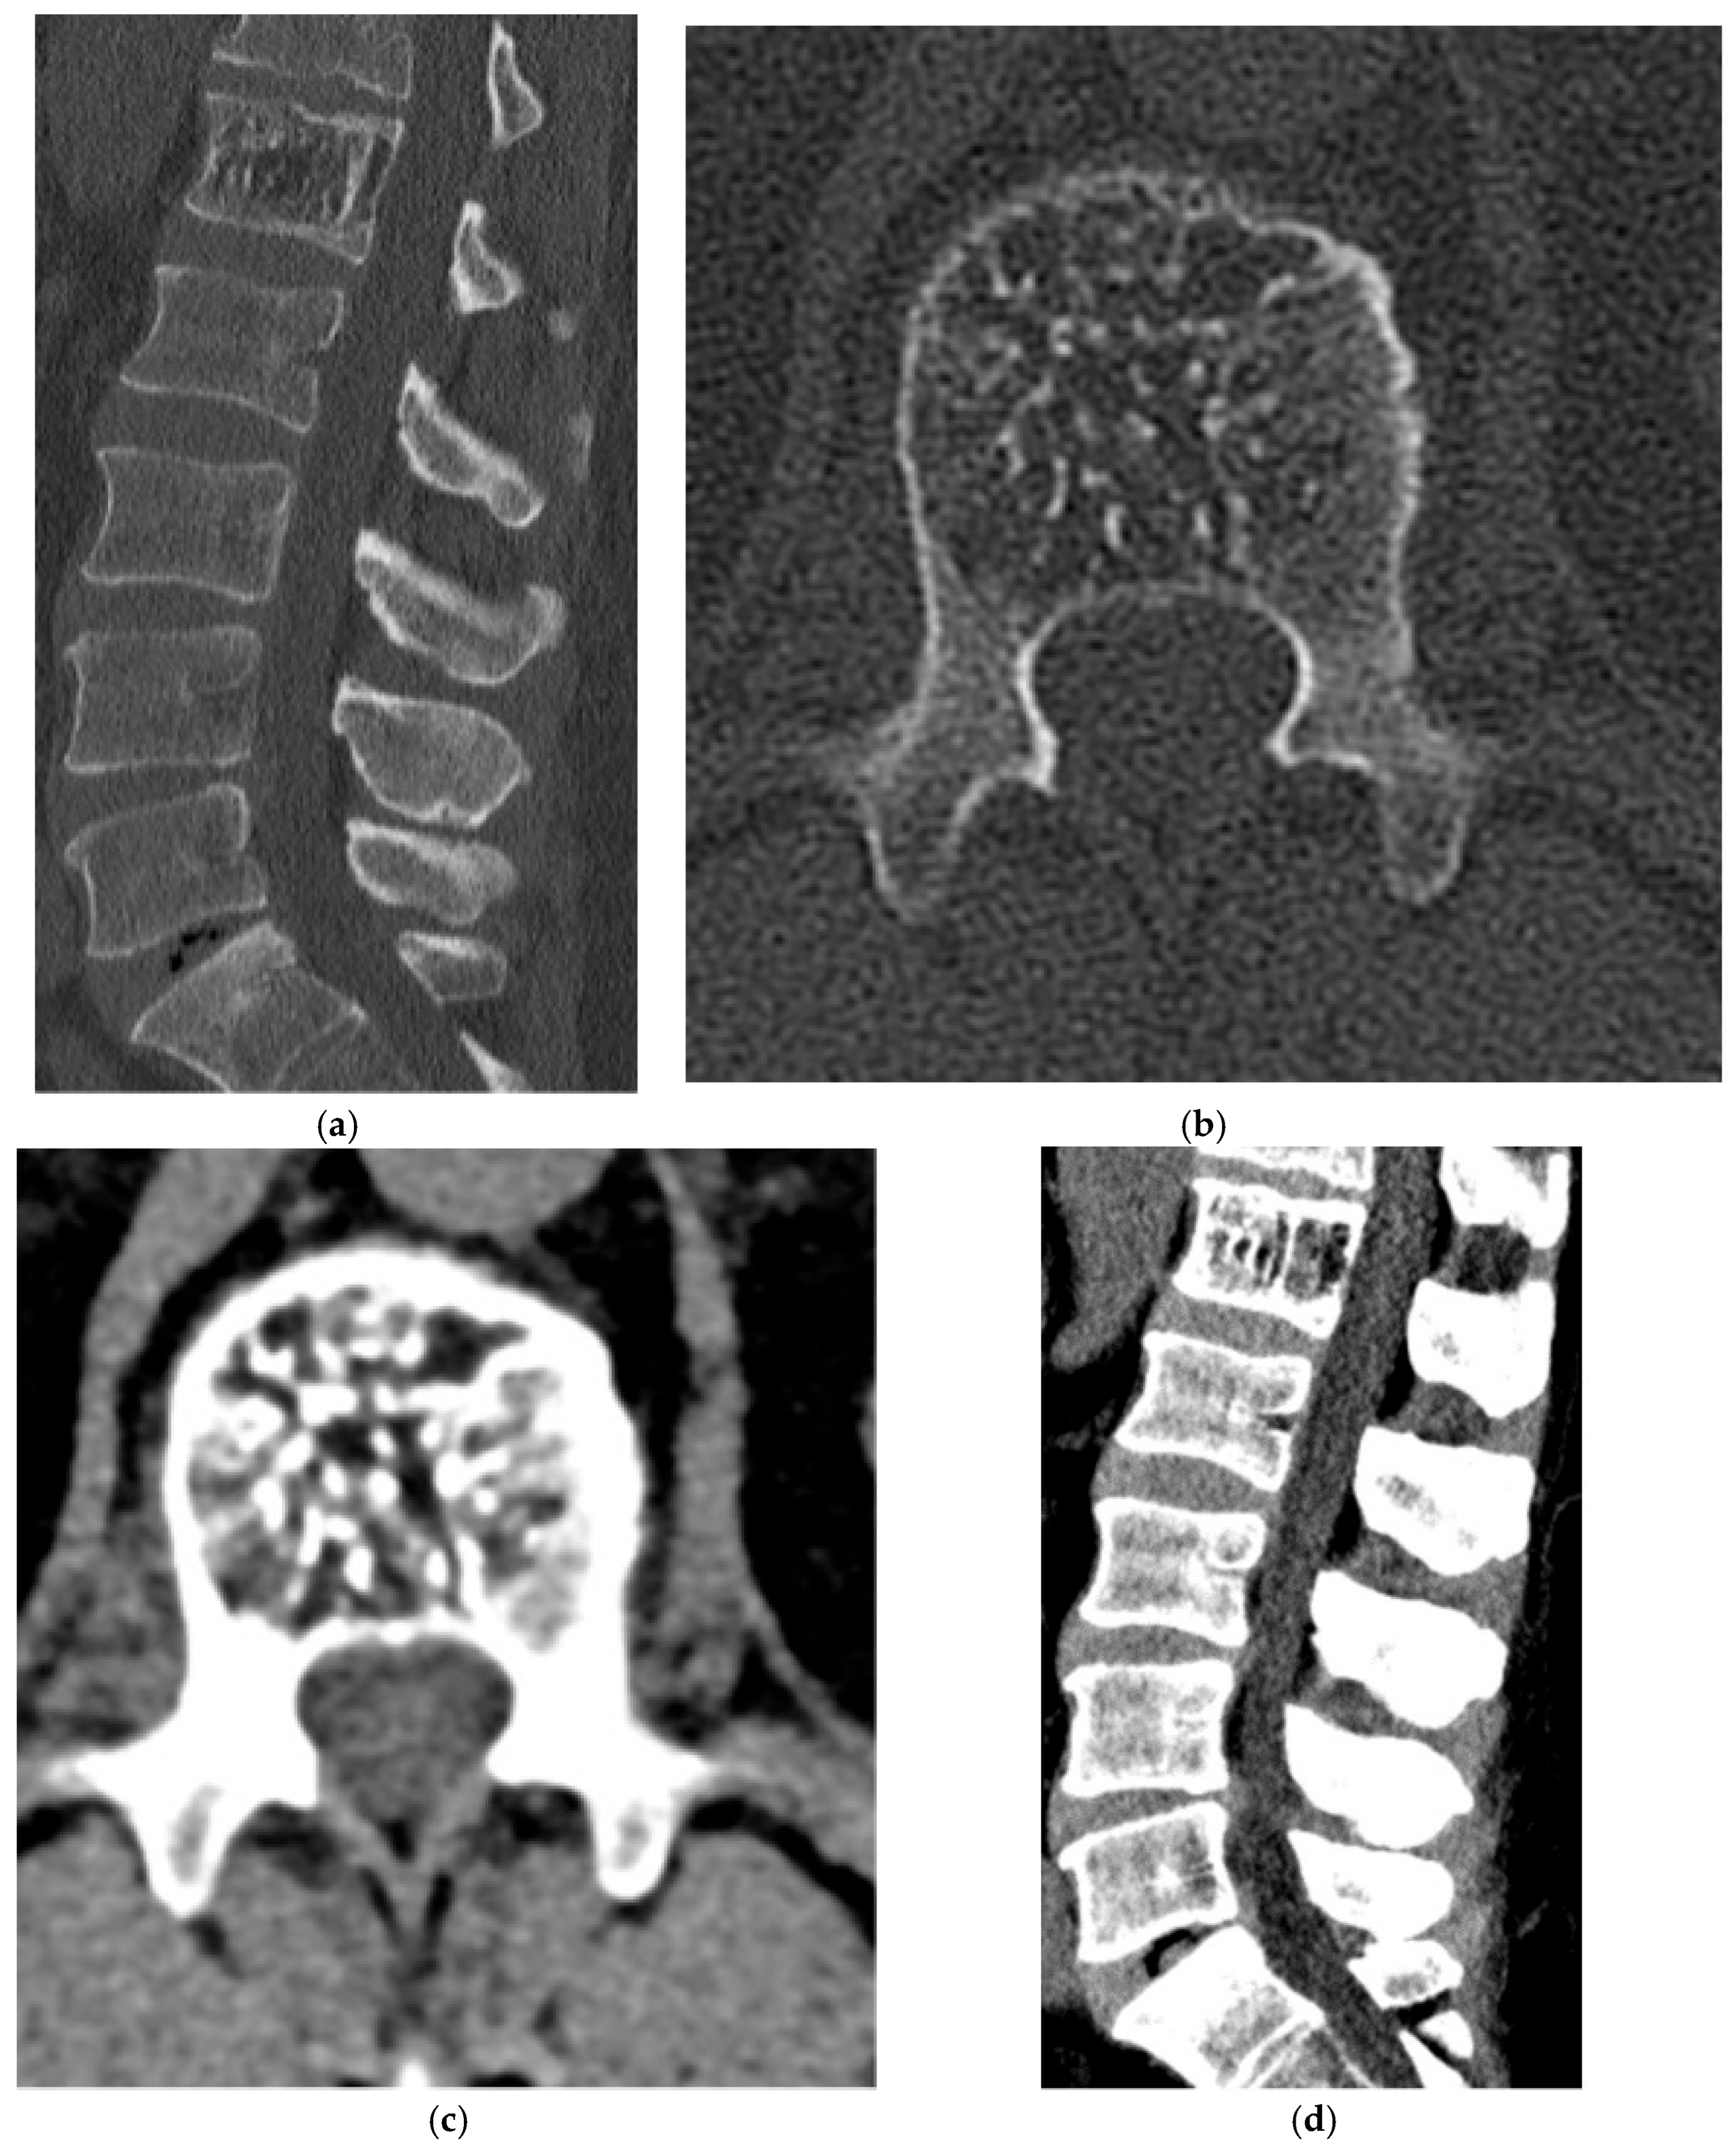

2.7. Osteoclast-Rich Stromal

Giant Cell Tumor